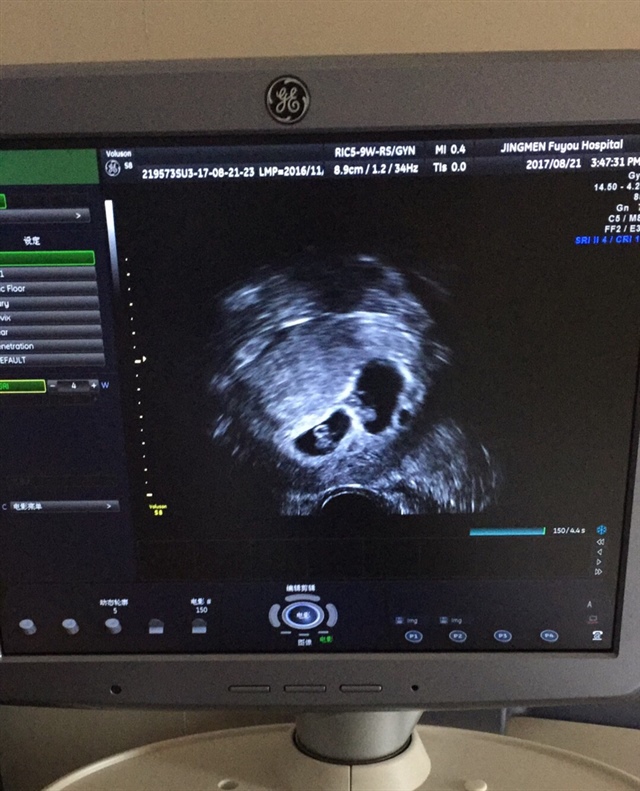

应该过了三个月就稳定了,看你这个是两个孕囊吧,两个孕囊有可能是龙凤胎,一个孕囊双胎的宝宝性别是一样的

木一[帖主]:是啊,两个孕囊,现在就是担心小便有少量的血丝